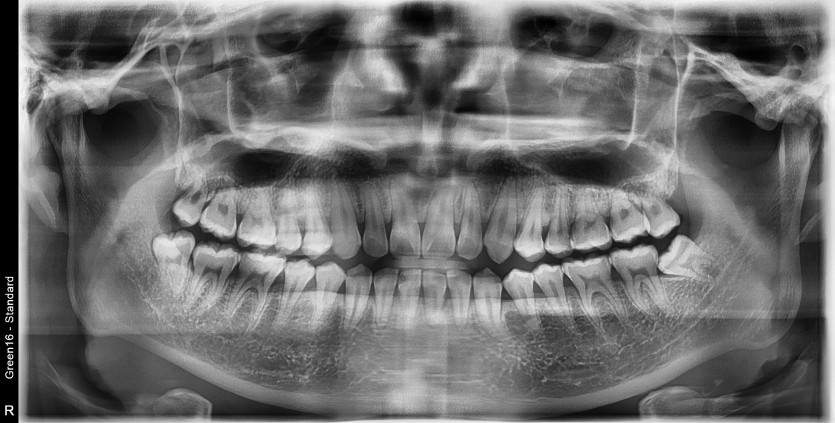

#18,48 사랑니 발치

구강 외과 전문의가 당일 발치했습니다.